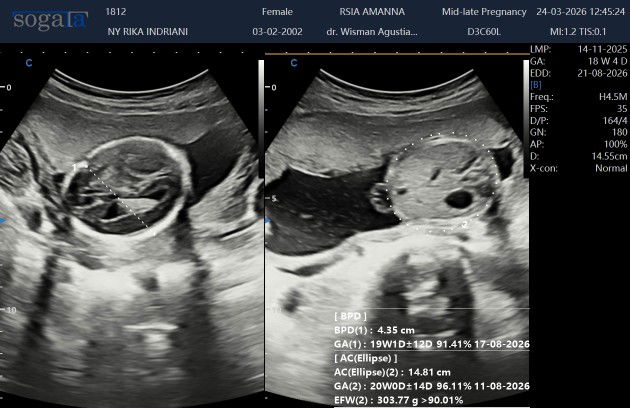

Hasil USG #mohonbantujawabbunda🥲🥲🥲

Bun ada yang sama gak di 20 minggu pas di USG tapi foto bayinya msh blm jelas. Itu normal gak ya bun atau ad yang sama?? 🥲#mohonbantujawabbunda